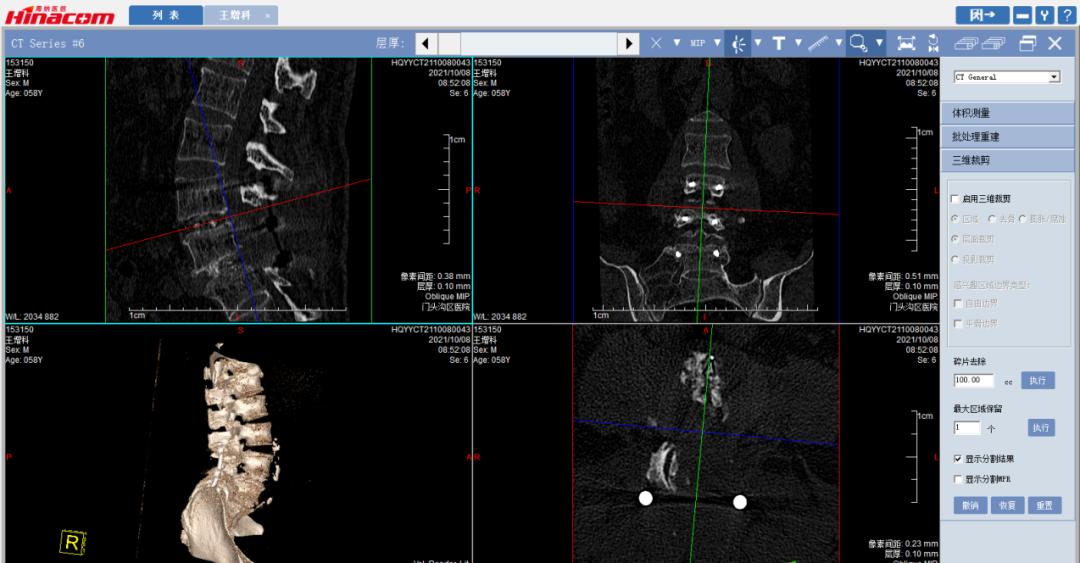

经匡正达主任诊治后,发现患者有先天性腰椎骶化,极易误诊,如果间隙做错了,那后果不堪设想。又考虑到患者要干农活,如果单纯椎管减压,有术后不稳的可能,而且患者长期生理性脊柱侧弯,综合考虑,最终决定为患者实施腰椎管减压的同时,进行椎间植骨融合钉棒内固定术。

手术于2021年9月26日顺利实施。术后,患者十几年来的下肢麻木疼痛和跛行终于消失了! 可以堂堂正正的走路,让王某一下显得年轻了十几岁!

腰34椎间盘--术前CT

腰45椎间盘--术前CT